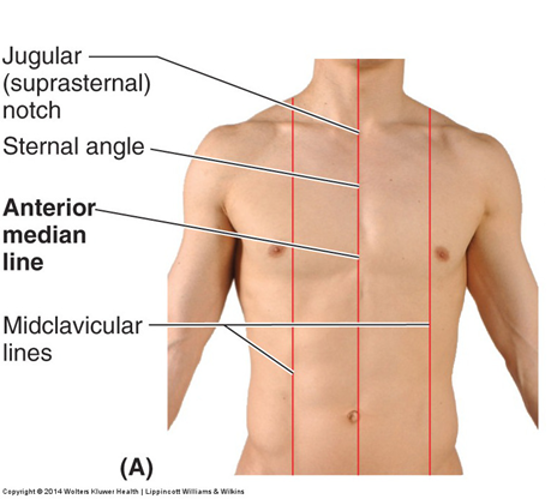

name the 2 anterior vertical lines and describe them?

the 2nd one is a little medial to what?

Anterior median (midsternal) line...vertical line through sternum in mid-sagittal plane

Midclavicular lines (MCL)...vertical through midpoints of the clavicles, parallel to median line...medial to the nipple

name the 2 posterior vertical lines and describe them?

another 2 names for the 1st one?

Posterior median (midspinal or midvertebral) line ...vertical line through spinous processes of vertebrae in mid-saggital plane

Scapular lines...vertical lines that pass through inferior angles of the scapula, line is parallel to posterior median line

posterior median line goes through the inferior angle of the scapula...look for it in the picture and try to picture the bottom of the scapula along the line